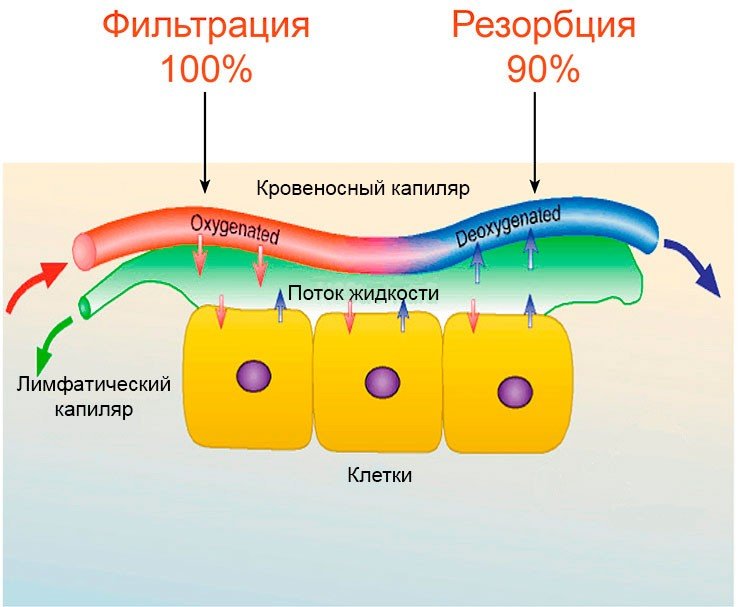

Изображения и схемы: как выглядит лимфа